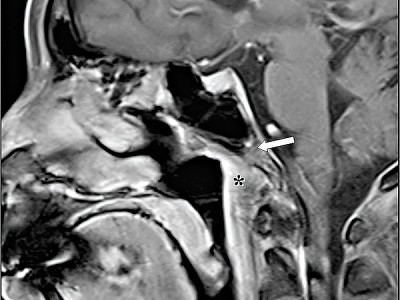

圖3:陳女士治療後的檢查圖片,腫瘤

明顯縮細。

張醫生原本利用誘導性化療,先把腫瘤縮細,但考慮到陳女士的情況,若用電療,其左眼視力定會喪失,故決定嘗試使用標靶藥配合化療。現時陳女士已達至無瘤腫狀態,亦可保存左眼的視力。